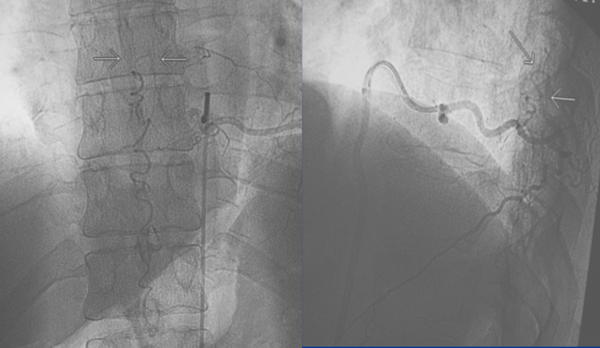

Figura 6: Caso #1. FDAVE recanalizada a los 15 meses post-embolización. ADM de frente (izquierda) y de perfil (derecha) las flechas blancas muestran el trayecto ascendente de la vena de drenaje. En el perfil se observa además que la vena de drenaje es dorsal.

CASO #1. Paciente masculino de 52 años con una historia de 6 meses de evolución de disestesias en ambos miembros inferiores, inestabilidad en la marcha, hiperreflexia y urgencia miccional. Se estudió con RMN (Fig. 3), ARM (Fig. 4) y ADM seguida de embolización con oclusión total de una FDAVE D8 izq. (Fig. 5). Evolucionó sin déficit y a los 11 meses comenzó con la misma sintomatología previa a la embolización. Se estudió nuevamente y la ADM (Fig. 6) mostraba la recidiva de la FDAVE y fue derivada para microcirugía (Fig. 7). Luego de la cirugía evolucionó sin déficit, se realizó una ADM diferida (Fig. 8) y lleva 116 meses libres de enfermedad.